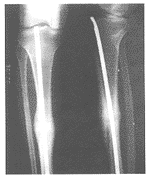

图1胫骨骨折术前X线片

图2胫骨骨折行非X线监测下尖头梅花

针闭合髓内固定术,术后三个月X线片

本组30例,随访时间为3~12个月。所有患者在3个月内骨折均骨性愈合,骨折端无成角、旋转、短缩畸形,无弯、断针,膝、踝关节功能正常,能正常行走,部分患者的伤肢功能已恢复到伤前水平(图1,2)。